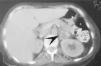

Una paciente de 46años, con historia de hipertensión arterial, acude alhospital por dolor subxifoideo opresivo, náuseas y disneaprogresiva, que hace necesaria su intubación yconexión a ventilación mecánica. Elelectrocardiograma (ECG) de ingreso muestra ritmo sinusal y datosde hipertrofia ventricular sin otros datos de interés, y uncorazón ecocardiográficamente normal. Durante losprimeros días presenta tendencia a la hipertensión.Evoluciona posteriormente con inestabilidad hemodinámica,por lo que ante la sospecha de un feocromocitoma se determinanmetanefrinas y ácido vanil mandélico en orina de 24horas, con valores respectivos de 10 mg (r.n. hasta 1 mg/24 h) y 18mg (r.n. hasta 5 mg/ 24 h). En la tomografía axialcomputarizada (TAC) abdominal (fig. 1) se observa unatumoración suprarrenal izquierda de 3 cm compatible confeocromocitoma; y la gammagrafía con131metaiodobencilguanidina (fig. 2) detecta un foco deactividad aumentada en área craneomedial delriñón izquierdo. La paciente fue tratada con alfabetabloqueantes y adrenalectomía evolucionandofavorablemente.